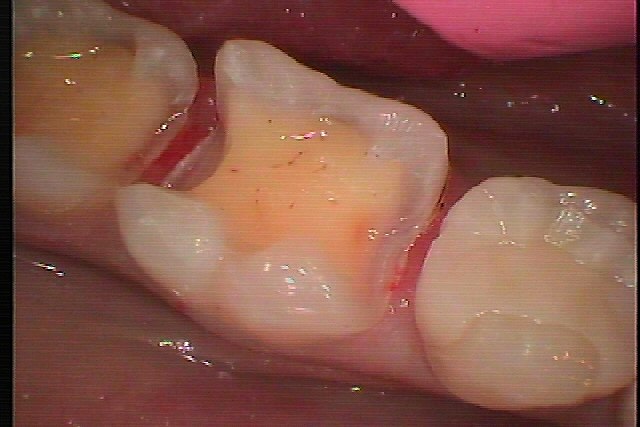

右下6,7番の銀歯から白いセラミックへやり変えていきます セラミックを用いた審美治療|お知らせ |広島市安佐南区の歯科医院 右下6,7番の銀歯から白いセラミックへやり変えていきます セラミックを用いた審美治療 トップ お知らせ・ブログ お知らせ 右下6,7番の銀歯から白いセラミックへやり変えていきます セラミックを用いた審美治療 右下6,7番の銀歯から白いセラミックへやり変えていきます セラミックを用いた審美治療 このような銀歯が入っています 側面から 銀歯を外していきました 6番には少し虫歯が認められました 虫歯を除去してCR樹脂にて覆罩を行い型取りを行っていきました CR樹脂にて覆罩を行い型取りを行っています セレック最新鋭のプライムスキャンを用いて本来の歯のように 修復を行いました Web診療予約 初めての方へ 選ばれ続ける理由 院内設備について 歯が痛いしみる一般歯科 歯がぐらぐらする歯周病 健康な歯を保ちたい予防歯科 子供の虫歯予防をしたい小児歯科 銀歯をセラミックに審美歯科 白い歯を目指しませんか?ホワイトニング 矯正専門医がいるので安心矯正歯科 抜けた歯を補いたいインプラント・入れ歯 医院案内 スタッフ紹介 メリィハウス歯科クリニックオフィシャルホームページ ラベンダー歯科クリニックオフィシャルホームページ お知らせ・ブログ ホーム 診療科目 一般歯科 歯周病治療 予防治療 小児歯科 審美治療 ホワイトニング 矯正歯科 入れ歯・インプラント マウスピース矯正 初めての方へ 院長・スタッフ 設備紹介 医院案内・アクセス メニューを閉じる